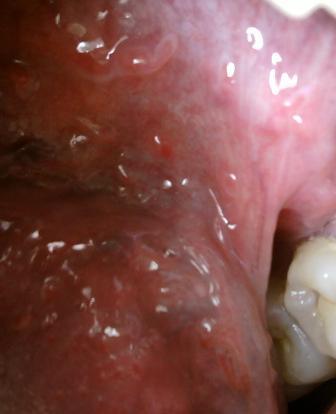

石家庄九州皮肤病医院 > 尖锐湿疣 > > > 巨大型尖锐湿疣应该如何治疗尖锐湿疣属于一种性病,发病部位是比较隐蔽的,因此专家在这里温馨提示:患病之后应该及时去正规的医院进行诊治,否则病情加重之后就会给疾病的治疗带来很大的困难。

巨大型尖锐湿疣应该如何治疗很多患者在患病初期没有得到及时有效的诊治,导致疾病加重,失去了治疗的最佳时期,后悔莫及。初期是治疗疾病的最佳时期,病情加重之后,治疗难度随之也会增加,因此专家温馨提示:对于疾病的诊治,应该抓紧时间治疗,即使是病情加重之后,也不要灰心沮丧,此时也应该选择一家权威规范的医院进行诊治。只要坚持诊治,疾病是可以达到比较理想的治疗效果的。